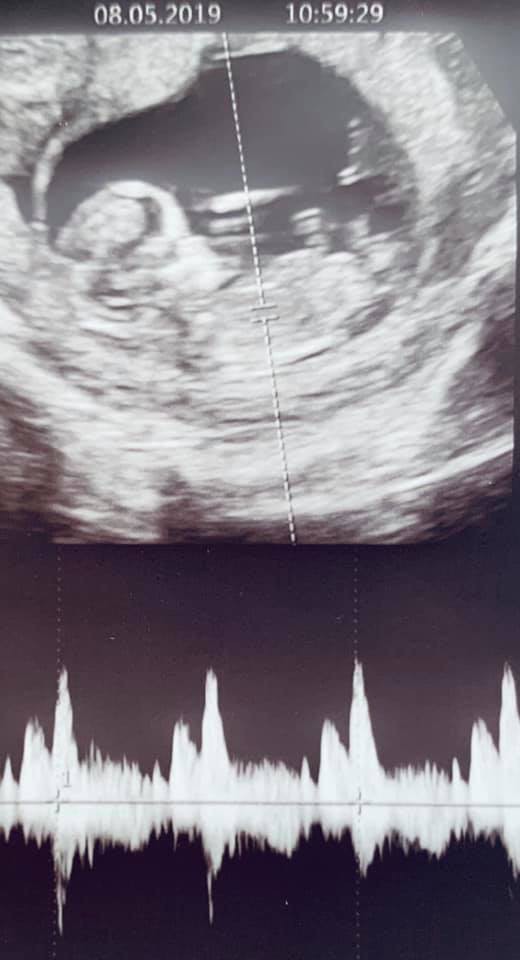

Theo đó, ngoài đăng bức ảnh siêu âm thai nhi, John Tuấn Nguyễn đã chia sẻ bằng tiếng Anh: “My lil’ bugga baby. The feels you get when you hear your kid’s heart beating healthy and they wave their hand at you from inside the womb. Life just got really real”. (Tạm dịch: Em bé của tôi. Cảm giác bạn có được khi nghe trái tim con bạn đập khoẻ mạnh và chúng vẫy tay với bạn từ trong bụng mẹ. Cuộc sống thật sự rất tuyệt vời”.

Ảnh siêu âm thai nhi được ông xã Lan Khuê chia sẻ lên trang cá nhân.